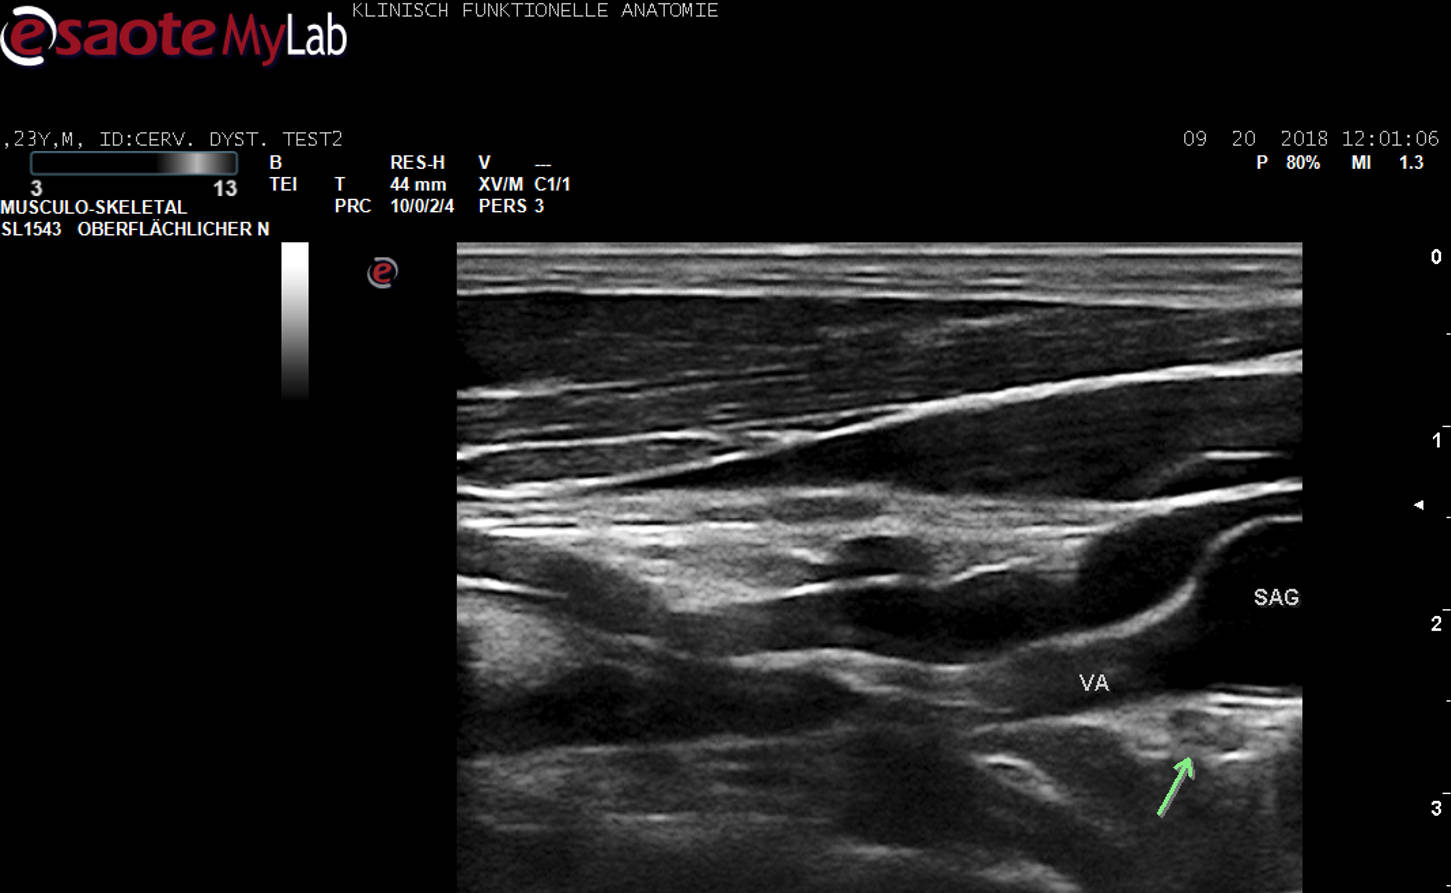

Weltweit erste US-Darstellung des Ganglion stellatum (grüner Pfeil) in unmittelbarer Nachbarschaft zur A. vertebralis (VA).